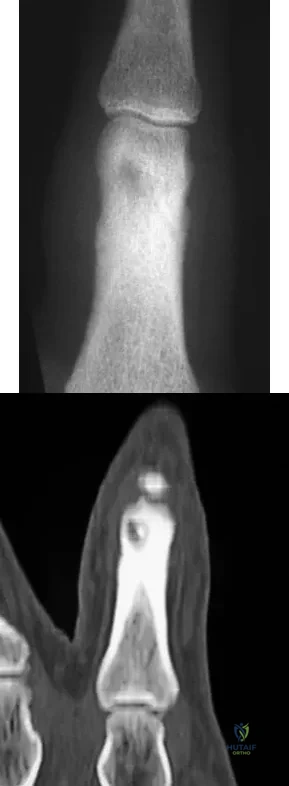

A 27-year-old man has had pain in the right index finger for the past 9 months. The pain is completely relieved with ibuprofen. An AP radiograph and CT scan are shown in Figures 80a and 80b. What is the most likely diagnosis?